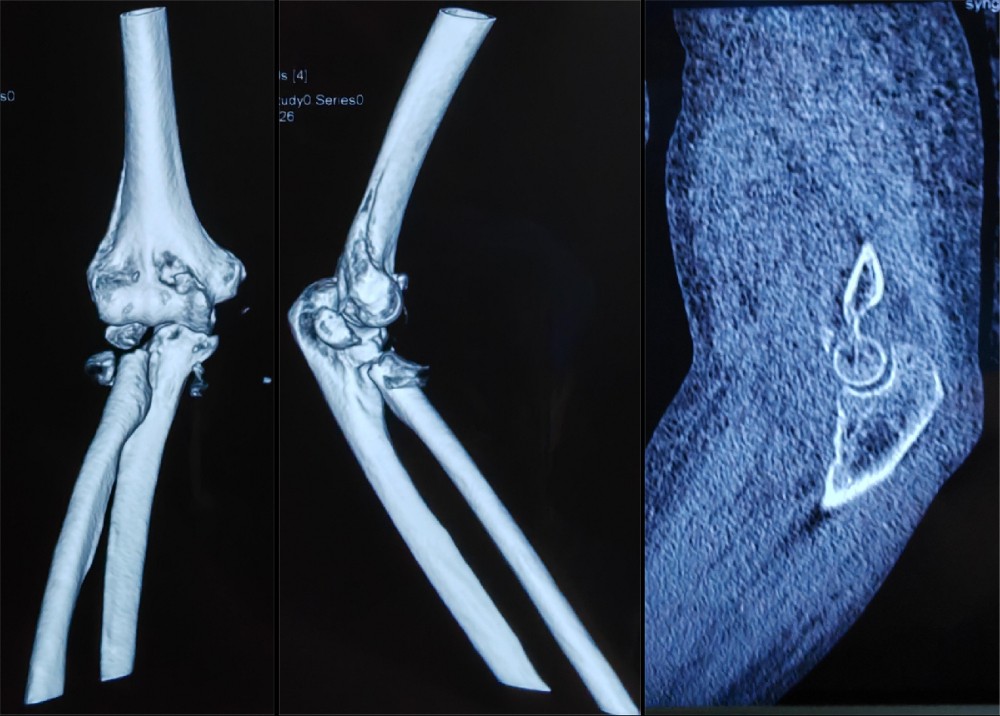

患者徐某,76岁,右肘部疼痛肿胀伴活动受限1天入院,患者于入院前1天,不慎被车从后侧撞伤,伤及右肘部,当时即感右肘部疼痛、畸形伴活动受限。受伤时患者否认头痛、头晕,胸闷、气短,恶心、呕吐等不适,被人救起后即赴某三甲医院就诊,行X光片检查显示:右肘关节脱位,右尺骨冠状突骨折,右桡骨头粉碎性骨折(肘关节恐怖三联征),给予手法复位肘关节脱位,患者为求进一步诊治赴我院门诊就诊,门诊以“1.右桡骨头粉碎性骨折2.右尺骨冠状突骨折”,收入我院创伤外科中心A区。

结合患者年龄及损伤类型,按照肘关节恐怖三联征的标准化治疗理念,副院长冯卫教授、创伤外科中心A区团队与李庭教授充分沟通、讨论后,由李庭教授及冯卫教授团队共同为患者施行标准化的治疗:“单一肘关节外侧切口,进行右冠状突骨折切开复位内固定术,右桡骨头粉碎性骨折桡骨头置换术,右肘关节外侧副韧带修复术,术中见右肘关节仍不稳定,随后给予右肘关节外固定架固定术”。标准化的治疗流程,使得这位高龄患者达到了与北京积水潭医院同质化的治疗。